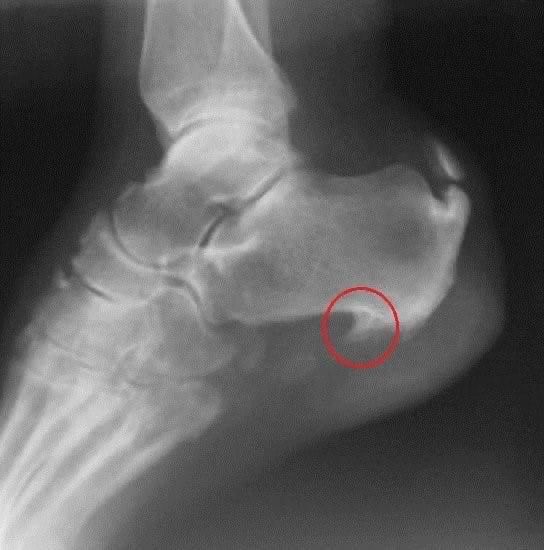

Los espolones no son sino una calcificación que produce una excrecencia ósea puntiaguda sobre el calcáneo, la parte inferior del hueso del talón.

El espolón se puede diagnosticar con una radiografía lateral del calcáneo, donde se reconoce una protuberancia orientada hacia los dedos y que puede variar entre 1 y 5 mm. No obstante, sería recomendable realizar otras pruebas, como análisis de sangre, para descartar otras enfermedades como artritis reumatoide, espondilitis anquilosante o gota.